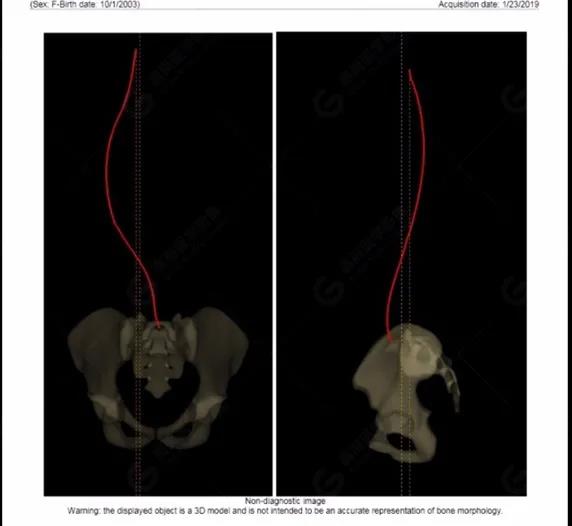

拍攝完畢后利用系統(tǒng)自帶的 Ster EOS 3D工作站對圖像進行后處理,自動生成臨床常用的參數(shù)值以及DICOM圖像,如圖所示:(2019-01-23)

脊柱側(cè)彎最重要一個臨床參數(shù)是側(cè)彎角(Cobb角),目前臨床公認(rèn)的Cobb角>10 °診斷為脊柱側(cè)彎;如Cobb角進行性持續(xù)性增加>40 °需要手術(shù)矯正治療。

本例患者胸椎右側(cè)彎,Cobb角(T6/T12)為47°,遂行手術(shù)矯正治療。術(shù)后多次隨訪的Cobb角(T10/L3)為12°-15°之間,較術(shù)前明顯縮小。

EOS在超低輻射劑量的情況下,保證高信噪比和高對比度的影像質(zhì)量。EOS 3D建模提供了精準(zhǔn)的自動臨床數(shù)據(jù)測量,避免了人工測量誤差,真正實現(xiàn)了骨放射領(lǐng)域的精準(zhǔn)治療、數(shù)字化建設(shè)與國際同步。術(shù)前計劃更加精準(zhǔn),術(shù)后評估從定性向定量轉(zhuǎn)變,更加客觀真實。EOS具有成像速度快、輻射劑量小、可模擬三維重建等優(yōu)點,尤其適合脊柱側(cè)彎患兒的篩查及定期隨訪。